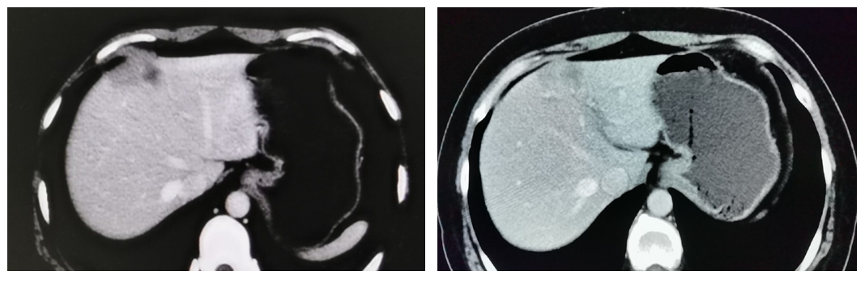

2020年1月至2020年9月继续氟维司群+戈舍瑞林治疗(9个月),每3个月定期复查肝转移灶稳定。

④三线治疗:2012年10月全面复查,腹部CT及MR提示:肝内部分转移灶较前明显增大,最大直径约3.9×1.8 cm(图5)。

图5.2020-10-08复查CT及MR提示:肝内部分转移灶较前明显增大,最大直径约3.9cm。

患者内分泌治疗的无进展生存期(PFS)为27个月,中间有8个月联合CDK4/6抑制剂治疗,肝内病灶缩小明显。建议患者再次使用CDK4/6抑制剂,内分泌药物换成芳香化酶抑制剂(AI),患者因经济原因拒绝。给予白蛋白紫杉醇(200 mg d1、8)化疗6周期,期间每2周期复查一次。CT提示复查肝转移较前缩小,疗效评价为稳定(SD)(图6)。